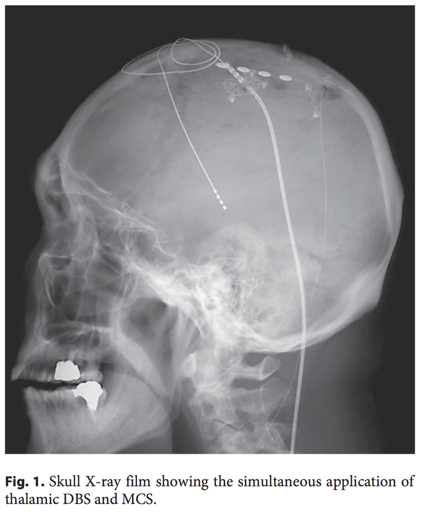

La référence Son BC, Kim DR, Kim HS, Lee SW. Simultaneous Trial of Deep Brain and Motor Cortex Stimulation in Chronic Intractable Neuropathic Pain. Stereotact Funct Neurosurg. Jul 26 2014; 92(4):218-226. L'article La stimulation corticale motrice (SCM) et cérébrale profonde (SCP) du nucleus ventralis caudalis (Vc) du thalamus ont démontré leur efficacité dans la douleur neuropathique chronique. La modulation de l'activité thalamique et thalamocortical serait considérée comme un...